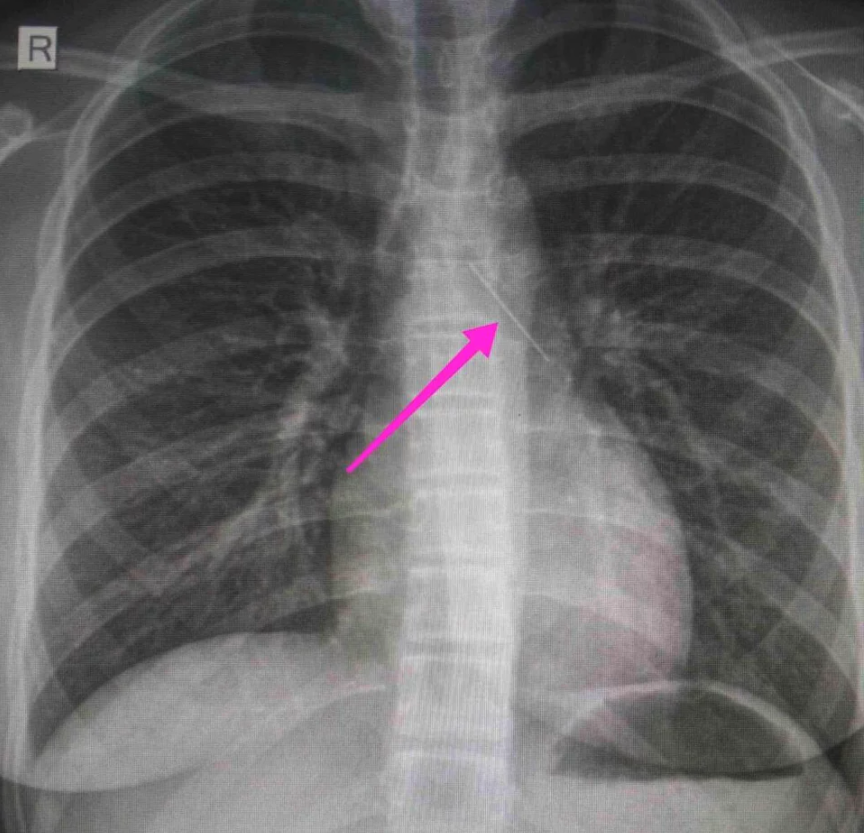

Η ανήλικη υπεβλήθη σε βρογχοσκόπηση και διαπιστώθηκε η μετακίνηση και ενσφήνωση του αντικειμένου στον δεξιό κύριο βρόγχο. «Μετά από εργώδεις προσπάθειες ολοκληρώθηκε με επιτυχία η αφαίρεσή της», δηλώνει το νοσοκομείο.

Κατά την βρογχοσκόπηση διαπιστώθηκε η μετακίνηση και ενσφήνωση του ξένου σώματος στον δεξιό κύριο βρόγχο. Μετά από εργώδεις προσπάθειες ολοκληρώθηκε με επιτυχία η αφαίρεση αυτού. Η ασθενής ανένηψε πλήρως εντός της χειρουργικής αίθουσας. Η ασθενής μεταφέρθηκε για παρακολούθηση και νοσηλεία στη Γ’ Παιδιατρική Κλινική.